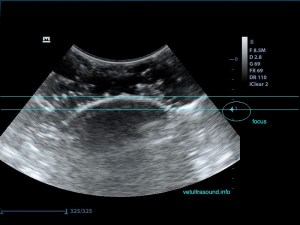

2) Το βάθος (depth), δηλαδή το να φέρουμε στην οθόνη του υπερήχου όσο το δυνατόν πιο κοντά το αντικείμενό μας, ώστε να καλύπτει σχεδόν τα 2/3 της οθόνης μας.

Μειώνουμε το βάθος ώστε να φέρουμε κοντά μας το αντικείμενο.

4) Το focus, δηλαδή την εστίαση της δέσμης, όσο πιο κοντά βρίσκεται σε αυτό που θέλουμε να μελετήσουμε τόσο καλύτερη εικόνα έχουμε.